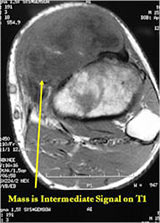

MRI:

- Mass on surface of bone

- Intermediate signal on T1 weighted images and high signal on T2 consistent with cartilage